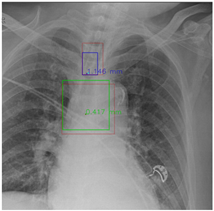

Figure 7 and Figure 8 demonstrate the effect of post-processing. The red bboxes and points in these figures are the GT ETT/bifurcation bboxes and the position of GT ETT tip/Carina, respectively. The green polygon is the GT mask of the ETT and the bifurcation. The blue bbox and point are the predicted ETT bbox and ETT tip, respectively. The yellow bbox and point are the predicted bifurcation and Carina, respectively. Specifically, without the post-process, the model might leave more than one predicted ETT tip/Carina, such as where the red arrow points in Figure 7a. However, with the post-process, the extra points would be removed as shown in Figure 7b. Besides, with the refinement process in the post-process, the feature point of ETT tip/Carina could be further refined as shown in Figure 8. Concretely, the object error of Carina was corrected from 8.469 mm to 1.319 mm.

Figure 8.

Refining the feature point of ETT tip/Cairna by the bbox of ETT/Bifurcation. (a) Without post-process. (b) With post-process.